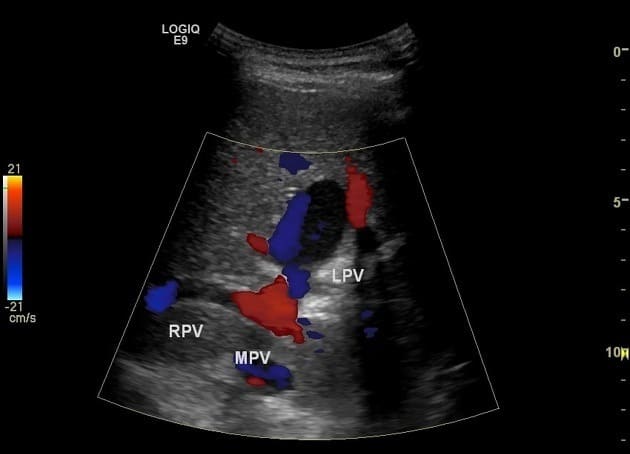

Phình TM cửa

» Thông tin: Nam giới – 90 tuổi.

» Lâm sàng: Kiểm tra sức khỏe.